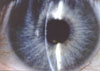

Cistinoza je autosomno recesivno nasledna bolest karkterisananakupljanjem velikih količina slobodnog cistina (nevezanog za proteine)u brojnim tkivima, naročito u rožnjači, konjunktivi, koštanoj srži,retikuloendotelnim ćelijama i u epitelnim ćelijama bubrežnih tubula.